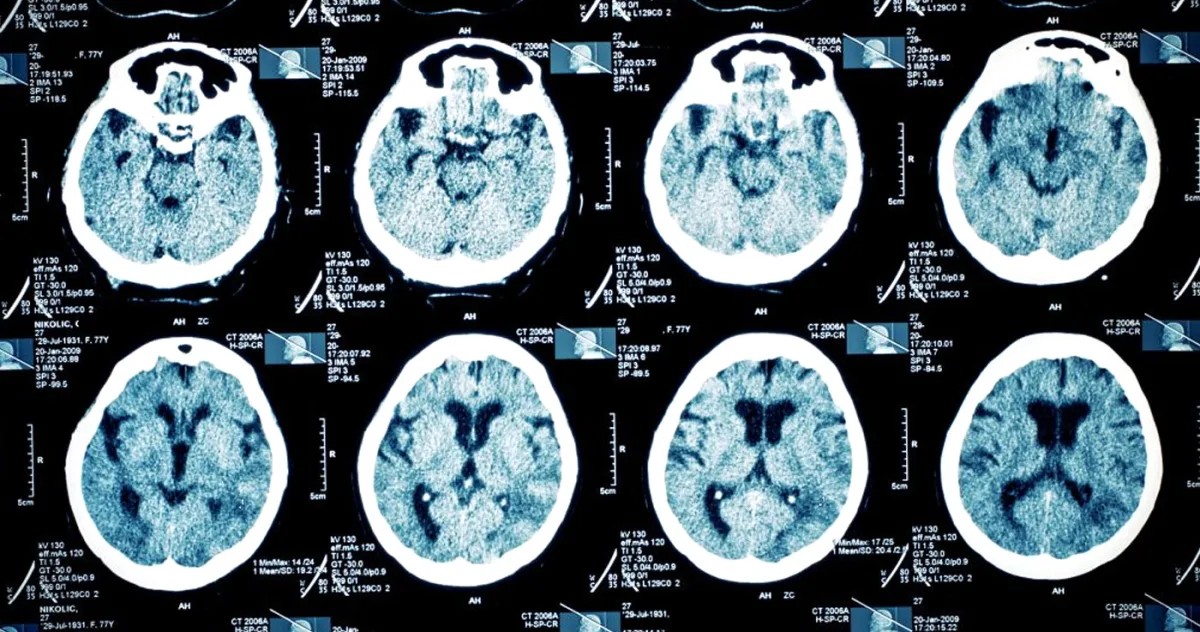

O echipă de cercetători de la Universitatea din Minnesota i-a propus să participe la un studiu ce evalua în premieră o formă de stimulare cerebrală minim invazivă, numită electrostimulare corticală adaptivă personalizată (PACE). Primul pas a fost crearea unei hărți precise a creierului său folosind RMN funcțional (RMNf). Această hartă, un fel de „brainotip” unic, a dezvăluit ceva neobișnuit.

Autorii studiului au descoperit că „rețeaua de saliență” a pacientului, o serie de regiuni cerebrale esențiale pentru a identifica semnalele importante din mediul înconjurător, era extrem de atipică. Aceasta era de patru ori mai mare decât la persoanele sănătoase, acoperind 12,4% din suprafața corticală – o particularitate asociată anterior cu depresia.